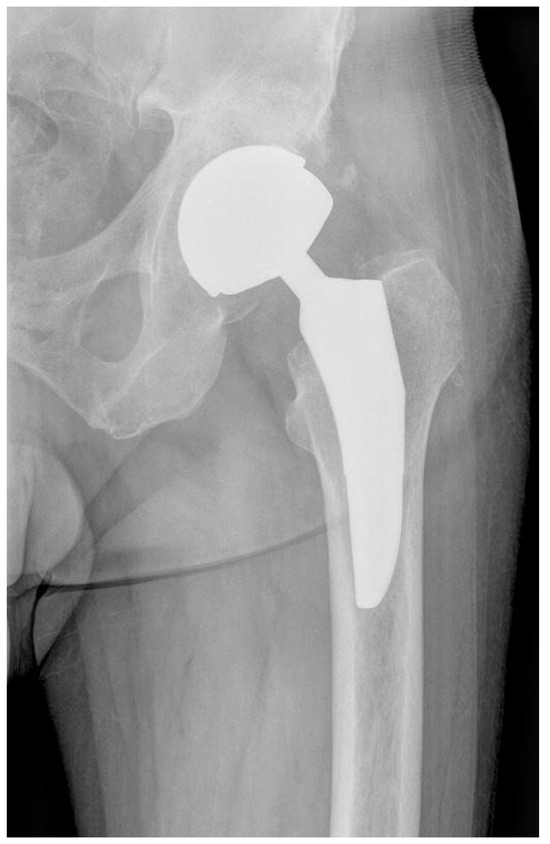

2.1. Description of the Studied Groups and Implants Used